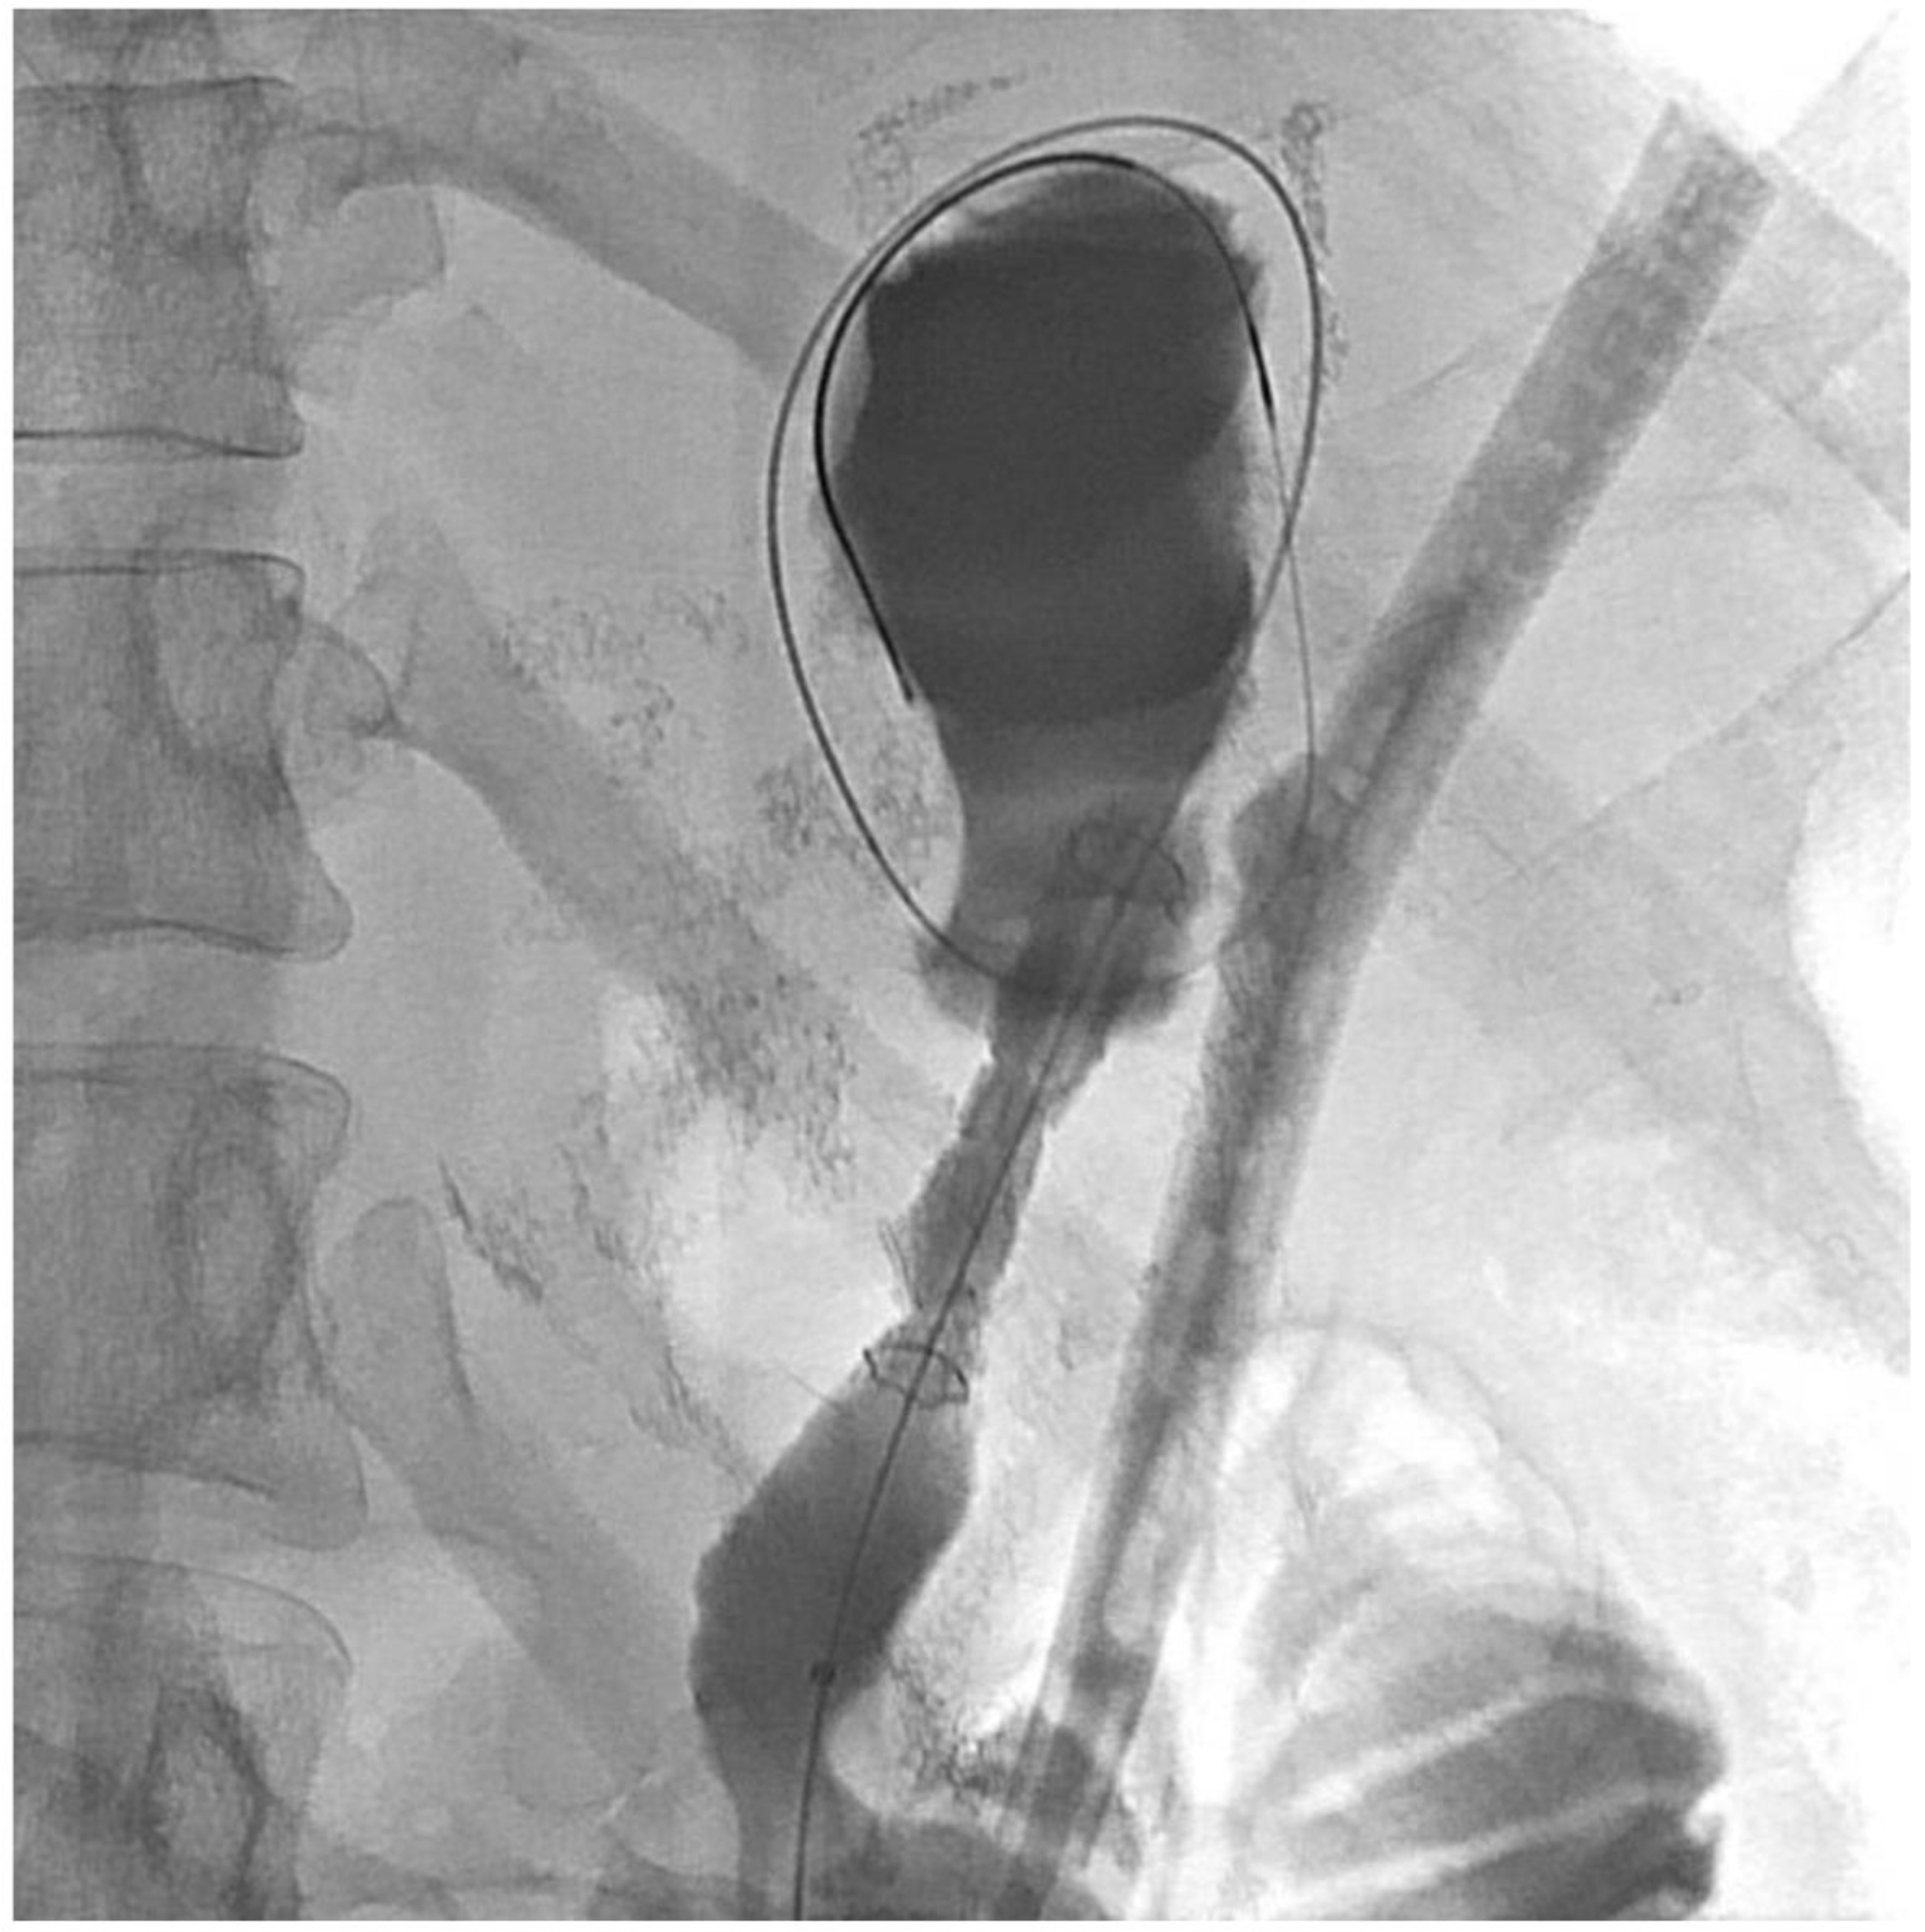

2. Detailed Case Description